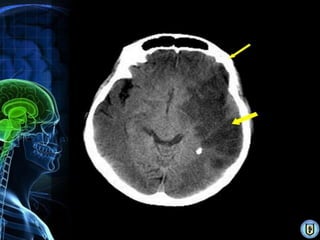

Diagnóstico

•   RMN (mejor para AVC isquémico)

•   Angiografía cerebral (Gold Standard)

•   TAC. (isquémico & hemorrágico)

•   Doppler transcraneal.

• 20.

Diagnóstico • RMN (mejor para AVC isquémico) • Angiografía cerebral (Gold Standard) • TAC. (isquémico & hemorrágico) • Doppler transcraneal.